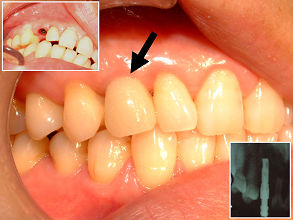

47歳女性:右側上顎犬歯を歯科インプラントで治療した写真